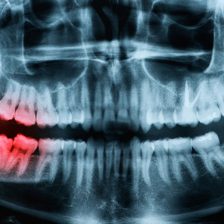

虫歯治療

根管治療